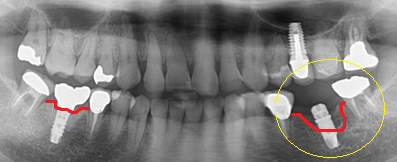

上記症例(黄色〇のところです)

50代女性の方です。いわゆるインプラント周囲炎です。

黄色〇で覆っていないほうのインプラント周りの赤線が本来の骨の位置です。黄色〇で覆っているほうはだいぶインプラント周りの骨が溶けている状態です。